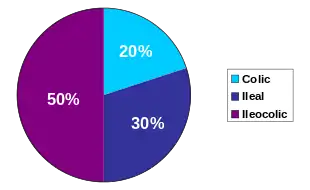

Crohn's disease is one type of inflammatory bowel disease (IBD). It typically manifests in the gastrointestinal tract and can be categorized by the specific tract region affected. A disease of both the ileum (the last part of the small intestine that connects to the large intestine), and the large intestine, Ileocolic Crohn's accounts for fifty percent of cases. Crohn's ileitis, manifest in the ileum only, accounts for thirty percent of cases, while Crohn's colitis, of the large intestine, accounts for the remaining twenty percent of cases and may be particularly difficult to distinguish from ulcerative colitis.